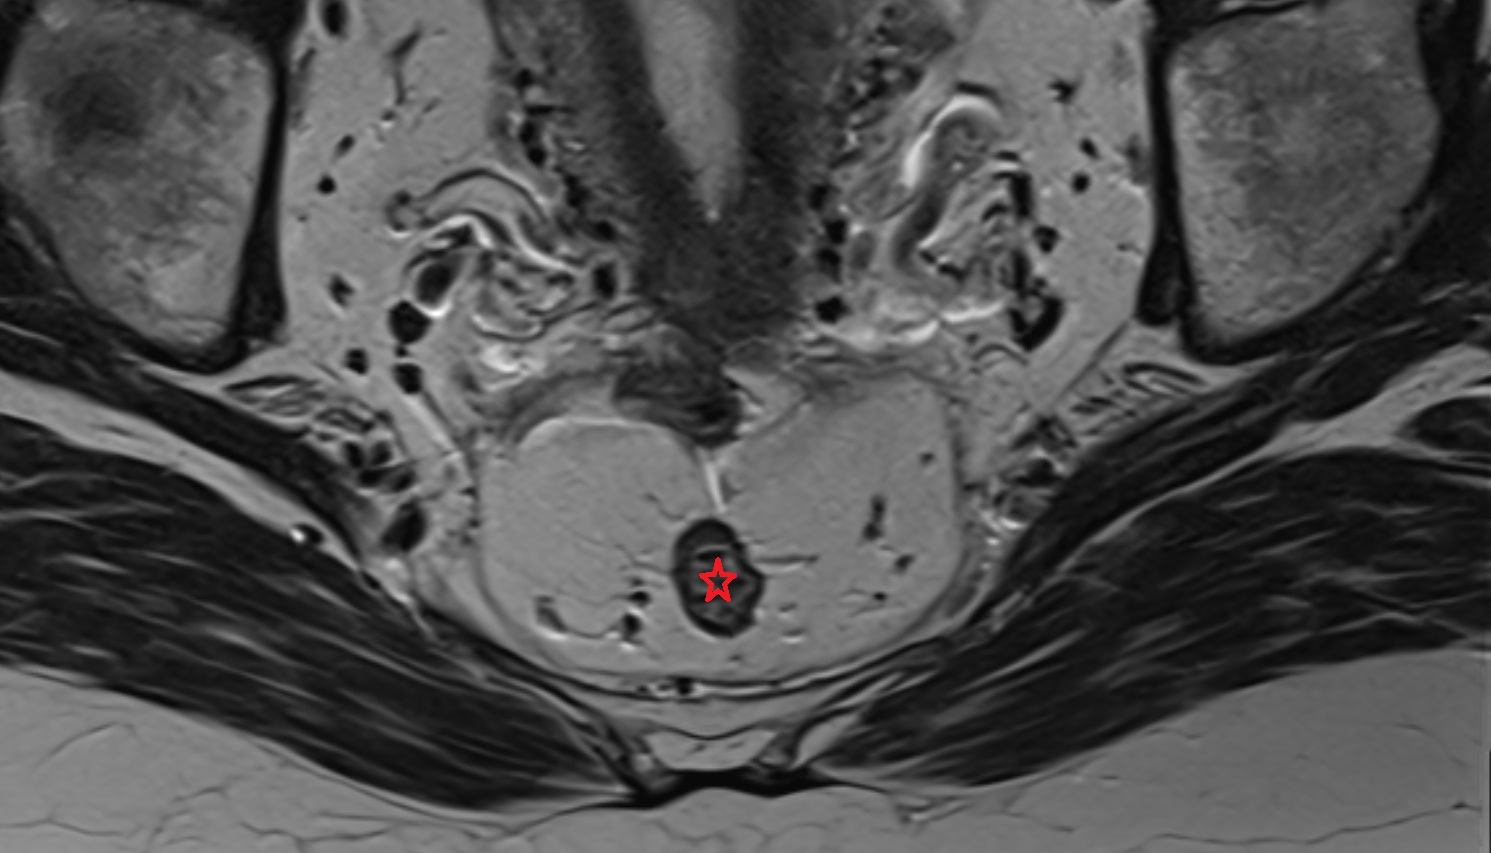

- Peripheral zone of prostate

- Anterior Fibromuscular Stroma of prostate

- Central zone of prostate

- Transitional zone of prostate

- Membranous urethra

- Prostatic urethra